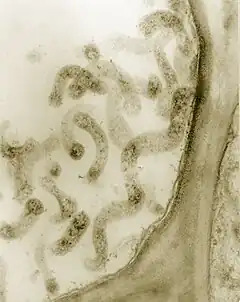

[2]Les Mollicutes sont une classe de bactéries du phylum des Mycoplasmatota. Son nom, tiré du latin mollis (mou) et cutis (peau) peut se traduire par « paroi molle ». Sur le plan morphologique, ces bactéries se distinguent en effet par leur petite taille (de l'ordre de 0,2 à 0,3 µm en général) et surtout par l'absence de paroi rigide. Leur membrane plasmique, néanmoins, est souvent partiellement rigidifiée par la présence de stérols. Leur génome est aussi remarquablement court, reflet d'un phénomène d'évolution réductive (en) en lien avec leur mode de vie habituellement parasite. Leur déplacement se fait le plus souvent par glissement, bien que le genre Spiroplasma soit doté d'une forme hélicoïdale qui permet à ces bactéries de se translater en tournant sur elles-mêmes à la manière des Spirochètes.

Ce sont donc des micro-organismes polymorphes (sphérique ou piriforme au filament hélicoïdal, ou ramifié). Ils sont généralement immobiles, mais certaines espèces peuvent se déplacer par « glissement », Ce sont généralement des bactéries à coloration Gram négatif, anaérobie facultatif.

Ce sont de très petits procaryotes (0,3 µm).